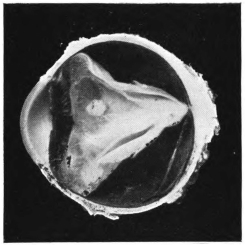

LENS DISLOCATED BETWEEN CILIARY BODY AND SCLERA

curly bracket span

11.

NUCLEUS OF CATARACT FREELY MOVABLE BETWEEN THE AQUEOUS AND VITREOUS CHAMBERS

12.

LENS IMPACTED IN ANGLE OF ANTERIOR CHAMBER

13.

CAPSULE OF MORGAGNIAN CATARACT IMPACTED IN ANGLE OF ANTERIOR CHAMBER

14.

LENS FLOATING FREE IN VITREOUS CHAMBER

15.

LENS LIGHTLY IMPRISONED IN EXUDATE INTO VITREOUS CAVITY